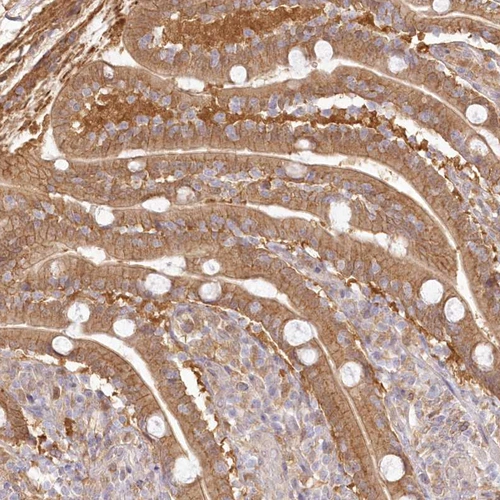

Immunohistochemical staining of human duodenum shows moderate cytoplasmic and membranous positivity in glandular cells.